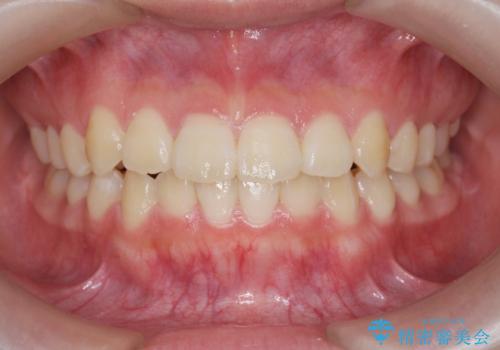

しっかりとゴムかけを頑張っていただいたおかげで、上顎臼歯の後方移動が達成されしっかりとした噛み合わせの構築と、八重歯の治療を達成することができました。